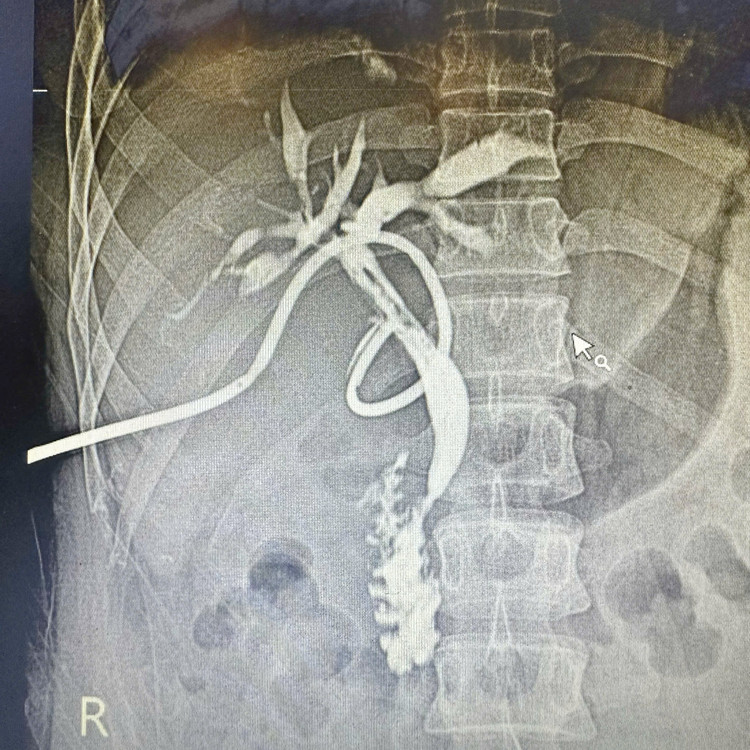

Người bệnh nhập viện trong tình trạng đau bụng kéo dài. Qua thăm khám lâm sàng và thực hiện các xét nghiệm cần thiết, đặc biệt là chụp cộng hưởng từ gan mật (MRI), các bác sĩ phát hiện hệ thống đường mật trong gan hai bên giãn. Đường mật gan phải có nhiều sỏi xếp chuỗi, viên lớn nhất kích thước khoảng 16 x 15 mm; ống mật chủ giãn 14 mm, chứa hai viên sỏi kích thước khoảng 15 mm.

Hình ảnh chụp cộng hưởng từ (MRI) cho thấy hình ảnh sỏi trong gan xếp chuỗi rất rõ (màu trắng) - Ảnh BVCC